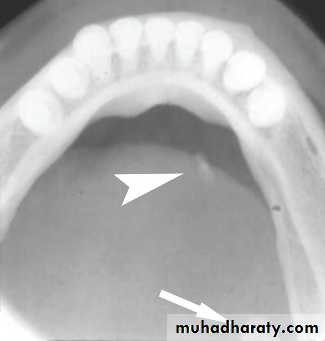

Stafne bone cyst, the most common ectopic salivary tissue.

Asymptomatic clearly demarcated radiolucency of the angle of the mandible.

No treatment